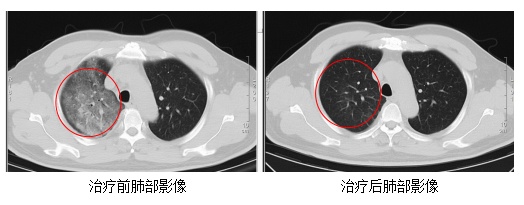

在感染科医护团队的精心治疗与细致护理下,顾先生的发热、咳嗽、胸闷等症状逐渐缓解。复查的CT结果显示,肺部炎症情况得到了明显的改善。目前,顾先生已经顺利康复出院。